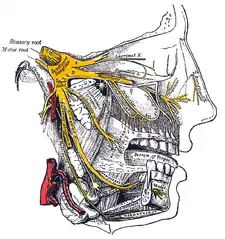

Origin

From the trigeminal ganglion, a single, large sensory root (radix sensoria s. portio major) enters the brainstem at the level of the pons. Immediately adjacent to the sensory root, a smaller motor root (radix motoria s. portio minor) emerges from the pons[3] slightly rostrally and medially to the sensory root.[4]

Motor fibers pass through the trigeminal ganglion without synapsing on their way to peripheral muscles, their cell bodies being located in the nucleus of the fifth nerve, deep within the pons.

Trigeminal ganglion

The three major branches of the trigeminal nerve—the ophthalmic nerve (V1), the maxillary nerve (V2) and the mandibular nerve (V3)—converge on the trigeminal ganglion (also called the semilunar ganglion or gasserian ganglion), located within Meckel's cave and containing the cell bodies of incoming sensory-nerve fibers. The trigeminal ganglion is analogous to the dorsal root ganglia of the spinal cord, which contain the cell bodies of incoming sensory fibers from the rest of the body.

Sensory branches

The ophthalmic, maxillary and mandibular branches leave the skull through three separate foramina: the superior orbital fissure, the foramen rotundum and the foramen ovale, respectively. The ophthalmic nerve (V1) carries sensory information from the scalp and forehead, the upper eyelid, the conjunctiva and cornea of the eye, the nose (including the tip of the nose, except alae nasi), the nasal mucosa, the frontal sinuses and parts of the meninges (the dura and blood vessels). The maxillary nerve (V2) carries sensory information from the lower eyelid and cheek, the nares and upper lip, the upper teeth and gums, the nasal mucosa, the palate and roof of the pharynx, the maxillary, ethmoid and sphenoid sinuses and parts of the meninges. The mandibular nerve (V3) carries sensory information from the lower lip, the lower teeth and gums, the chin and jaw (except the angle of the jaw, which is supplied by C2-C3), parts of the external ear and parts of the meninges. The mandibular nerve carries touch-position and pain-temperature sensations from the mouth. Although it does not carry taste sensation (the chorda tympani is responsible for taste), one of its branches—the lingual nerve—carries sensation from the tongue.

Trigeminal nerve in yellow Trigeminal ganglion

Trigeminal ganglion Cerebrum (deep inferior dissection)